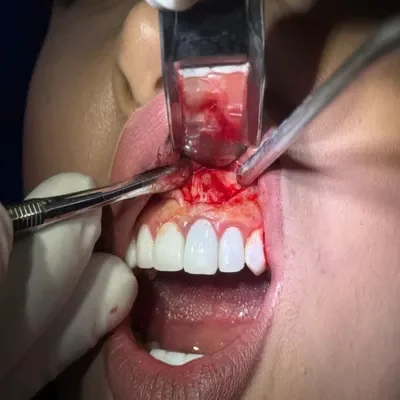

بهطور علمی، زمانیکه پوسیدگی از سطح مینا عبور کند و به عاج یا عصب برسد، دیگر درمان ساده کافی نیست و بیمار ناچار به درمان ریشه (عصبکشی) خواهد بود.

بنابراین، اگر هنگام خوردن مواد شیرین احساس تیرکشیدن یا درد متوسط دارید، باید در اولین فرصت به دندانپزشک مراجعه کنید.

دندانپزشک با بررسی دقیق و برداشتن پوسیدگیها، میتواند تنها در یک جلسه با انجام ترمیم ساده، دندان را نجات دهد و از پیشرفت آسیب جلوگیری کند.

در واقع، نادیدهگرفتن درد دندان با شیرینی میتواند باعث تبدیل یک درمان کوتاهمدت و کمهزینه به روندی طولانی و پرهزینه شود.